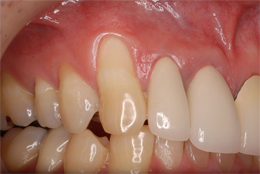

結合組織による根面被覆症例

- 主訴

- 右上3番がしみる

- 治療内容

- 右上3の歯頸部過度なブラッシングにより歯肉退縮したもので、右上口蓋より結合組織を採取し、歯根露出部に移植

- 治療費用

- CTG:60,000円(税別)

- 治療期間

- 術後3ヶ月の状態